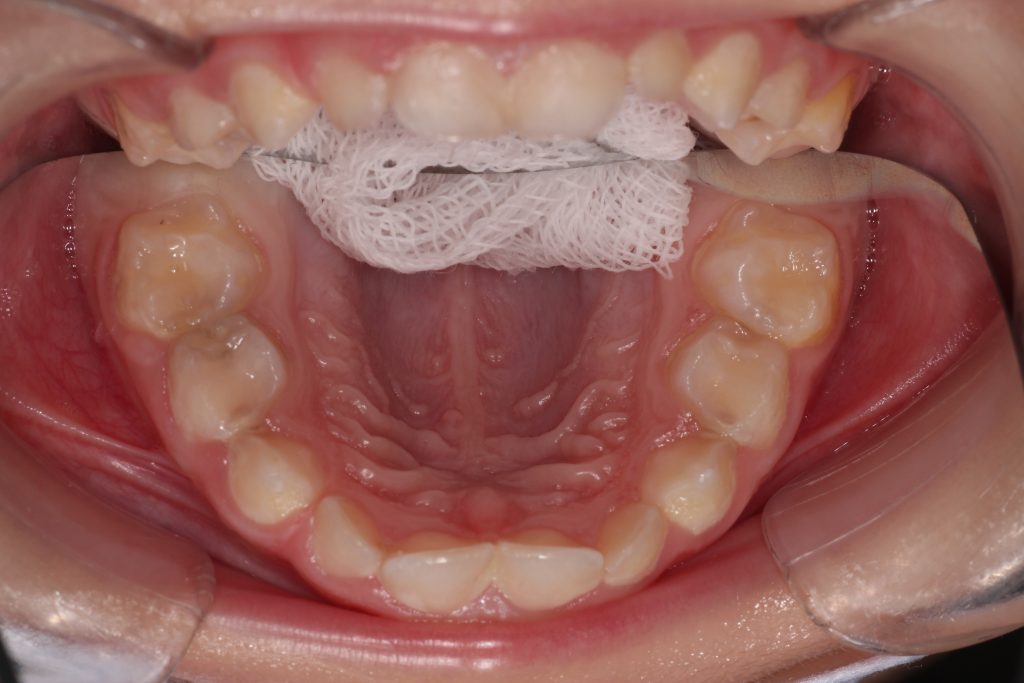

Sizce Bu Dişlerde Çürük Var mı?

Çürük dediğimizde, aklımıza hemen belirgin siyah noktalar geliyor. Ancak durum bazen böyle olmayabiliyor. Özellikle süt dişi çürükleri, arayüzlerden başlayıp, çiğneme yüzeyine doğru ilerlediği için, anne-babanın fark ettiği siyah nokta aşamasında, çürük tedavisi için geç kalınmış olabiliyor. Özellikle 5 yaşından küçük çocuklarda, 1 tane arayüz çürüğünün varlığı, bize geri kalan dişlerinin arasında da arayüz çürüğünün varlığını düşündürebiliyor.

Bu sebeple bu hastamızdan da hasta velilerine “çene filmi” dediğimiz, panoramik çene grafisi istedik. Hasta velisi için görünüşte 1 tane zannedilen çürüğün aslında, 8 süt azı dişinin 8’inde de olduğunu görmüş olduk. Süt dişi çürükleri çok hızlı ilerlediği ve sinirleri daha yüzeye yakın olduğundan hemen ağrı yaptıkları için, bu çürüklere de tedavi planladık.